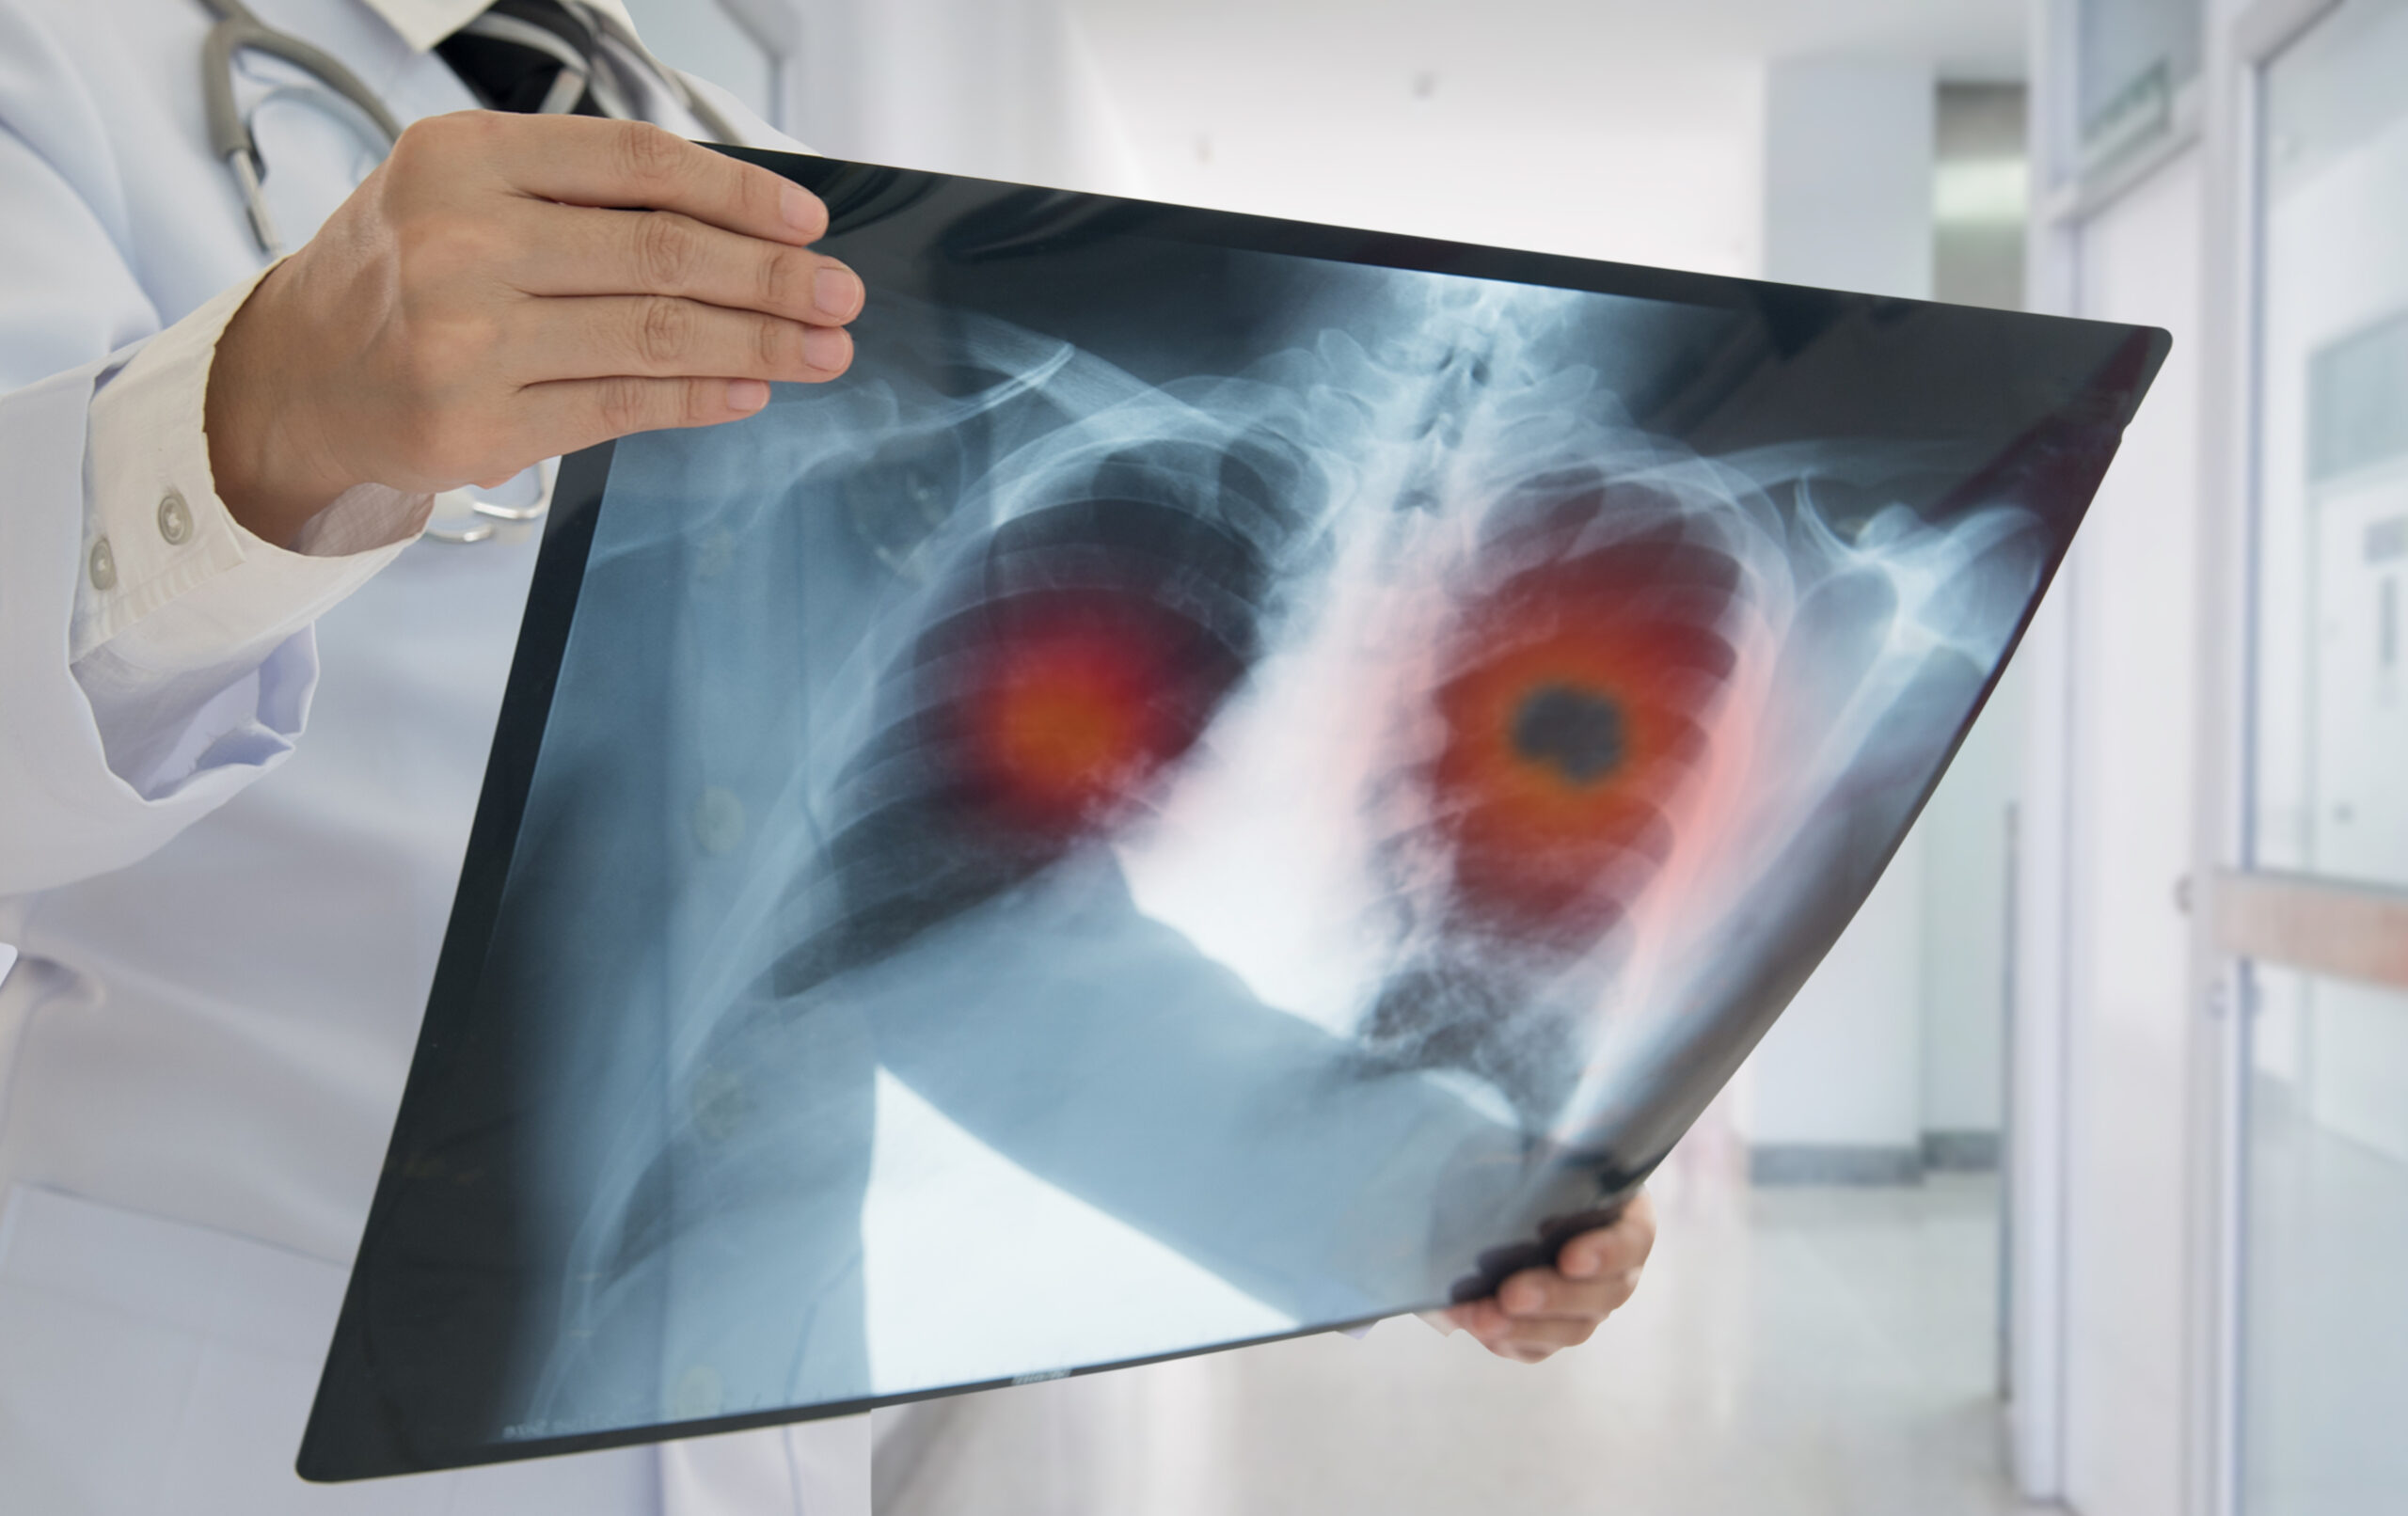

Lung Cancer Screening X Ray

Experience the clarity of Lung Cancer Screening X Ray with our curated collection of comprehensive galleries of images. featuring understated examples of photography, images, and pictures. designed to emphasize clarity and focus. Discover high-resolution Lung Cancer Screening X Ray images optimized for various applications. Suitable for various applications including web design, social media, personal projects, and digital content creation All Lung Cancer Screening X Ray images are available in high resolution with professional-grade quality, optimized for both digital and print applications, and include comprehensive metadata for easy organization and usage. Our Lung Cancer Screening X Ray gallery offers diverse visual resources to bring your ideas to life. Comprehensive tagging systems facilitate quick discovery of relevant Lung Cancer Screening X Ray content. Multiple resolution options ensure optimal performance across different platforms and applications. Time-saving browsing features help users locate ideal Lung Cancer Screening X Ray images quickly. The Lung Cancer Screening X Ray archive serves professionals, educators, and creatives across diverse industries. Instant download capabilities enable immediate access to chosen Lung Cancer Screening X Ray images. Whether for commercial projects or personal use, our Lung Cancer Screening X Ray collection delivers consistent excellence. Professional licensing options accommodate both commercial and educational usage requirements.